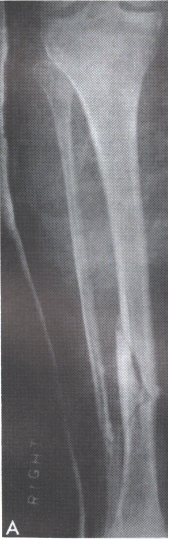

The accompanying picture demonstrates the size difference between the upper and lower tibia, and also shows a fracture of the lower tibia.

You've got a better chance of surviving a "hard lowish kick" if you use your upper tibia, as opposed to your lower tibia. It has some to do with conditioning (which, should make the bone stronger), but quite simply, more to do with physics. You see, it's a matter of size. Ain't it always.

The lower tibia is just not as large, diameter wise, as the upper tibia. It doesn't have the amount of bone or the strength of the upper tibia; this is why, with the exception of skiing injuries, lower tibial fractures are much more common than upper tibial fractures.

So, if you're planning on throwing a leg kick against something hard, like bone (lower leg), hit him with your upper tibia. The lower tibia is not strong enough to survive as well when it comes to striking the upper tibia. On other parts of the body, the lower tibia is fine, because, it is either stronger than other bony strike areas (such as the ribs or forearm), or, it is striking against an area with more muscle (thigh, upper arm).